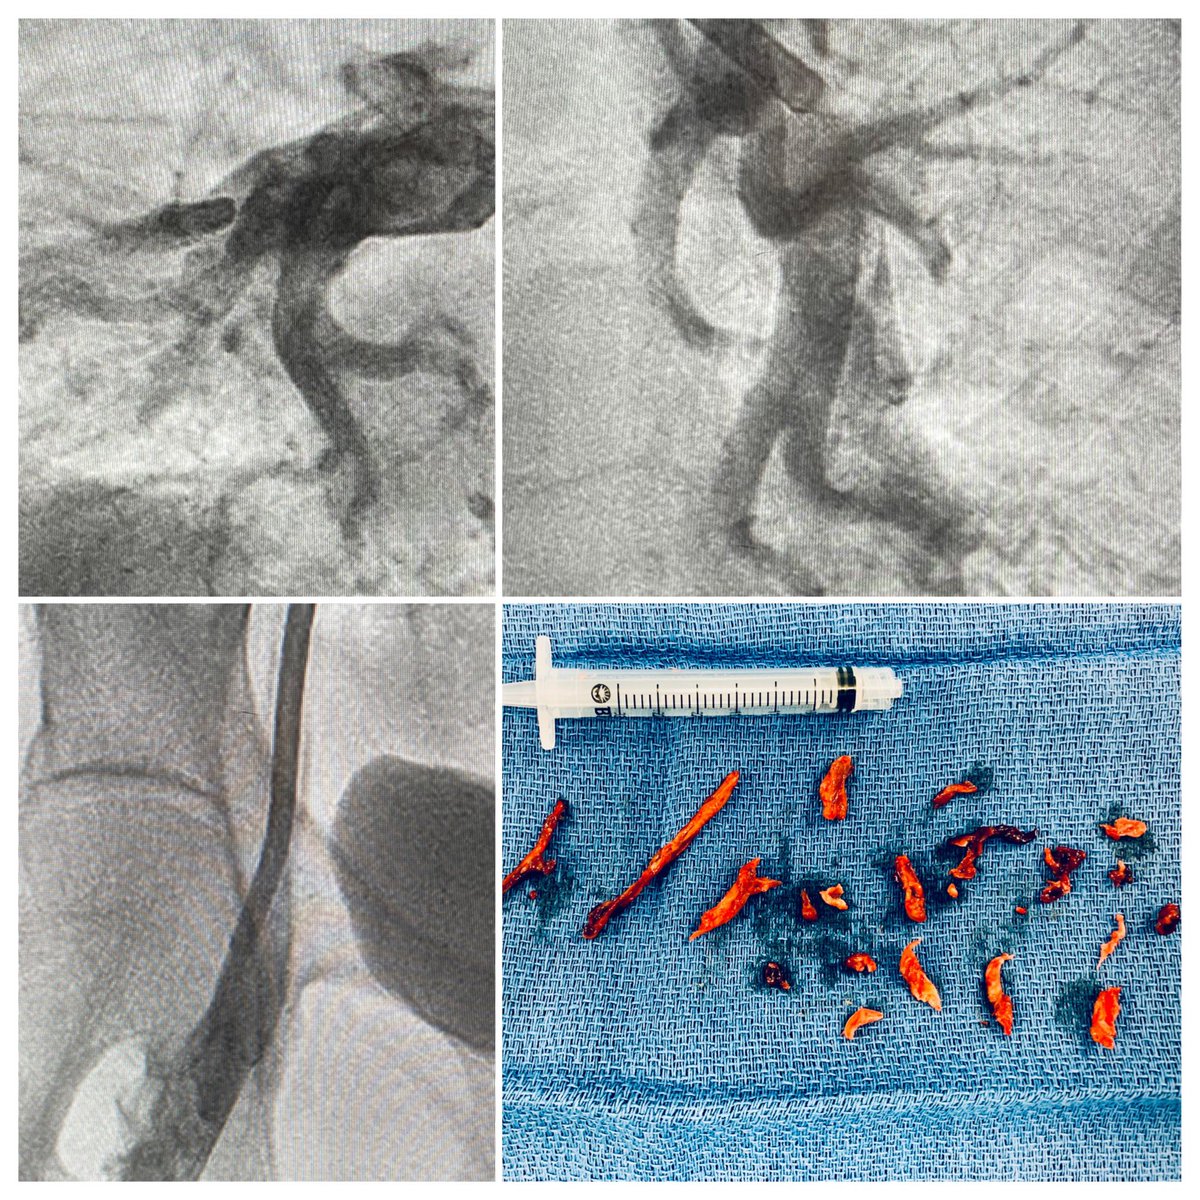

Masive PE with complete right pulmonary artery blockage and haemodynamic shock.Thrombus removing successfully. Another case using CAT12